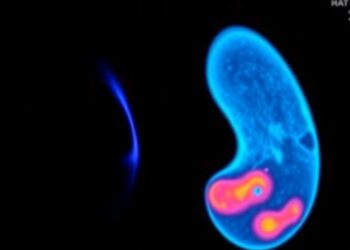

Ultrasound Boosts Lenvatinib’s Effects on Thyroid Cancer

Recent advancements in cancer treatment have unveiled the potential for technologically enhanced therapies to significantly improve outcomes for patients diagnosed ...